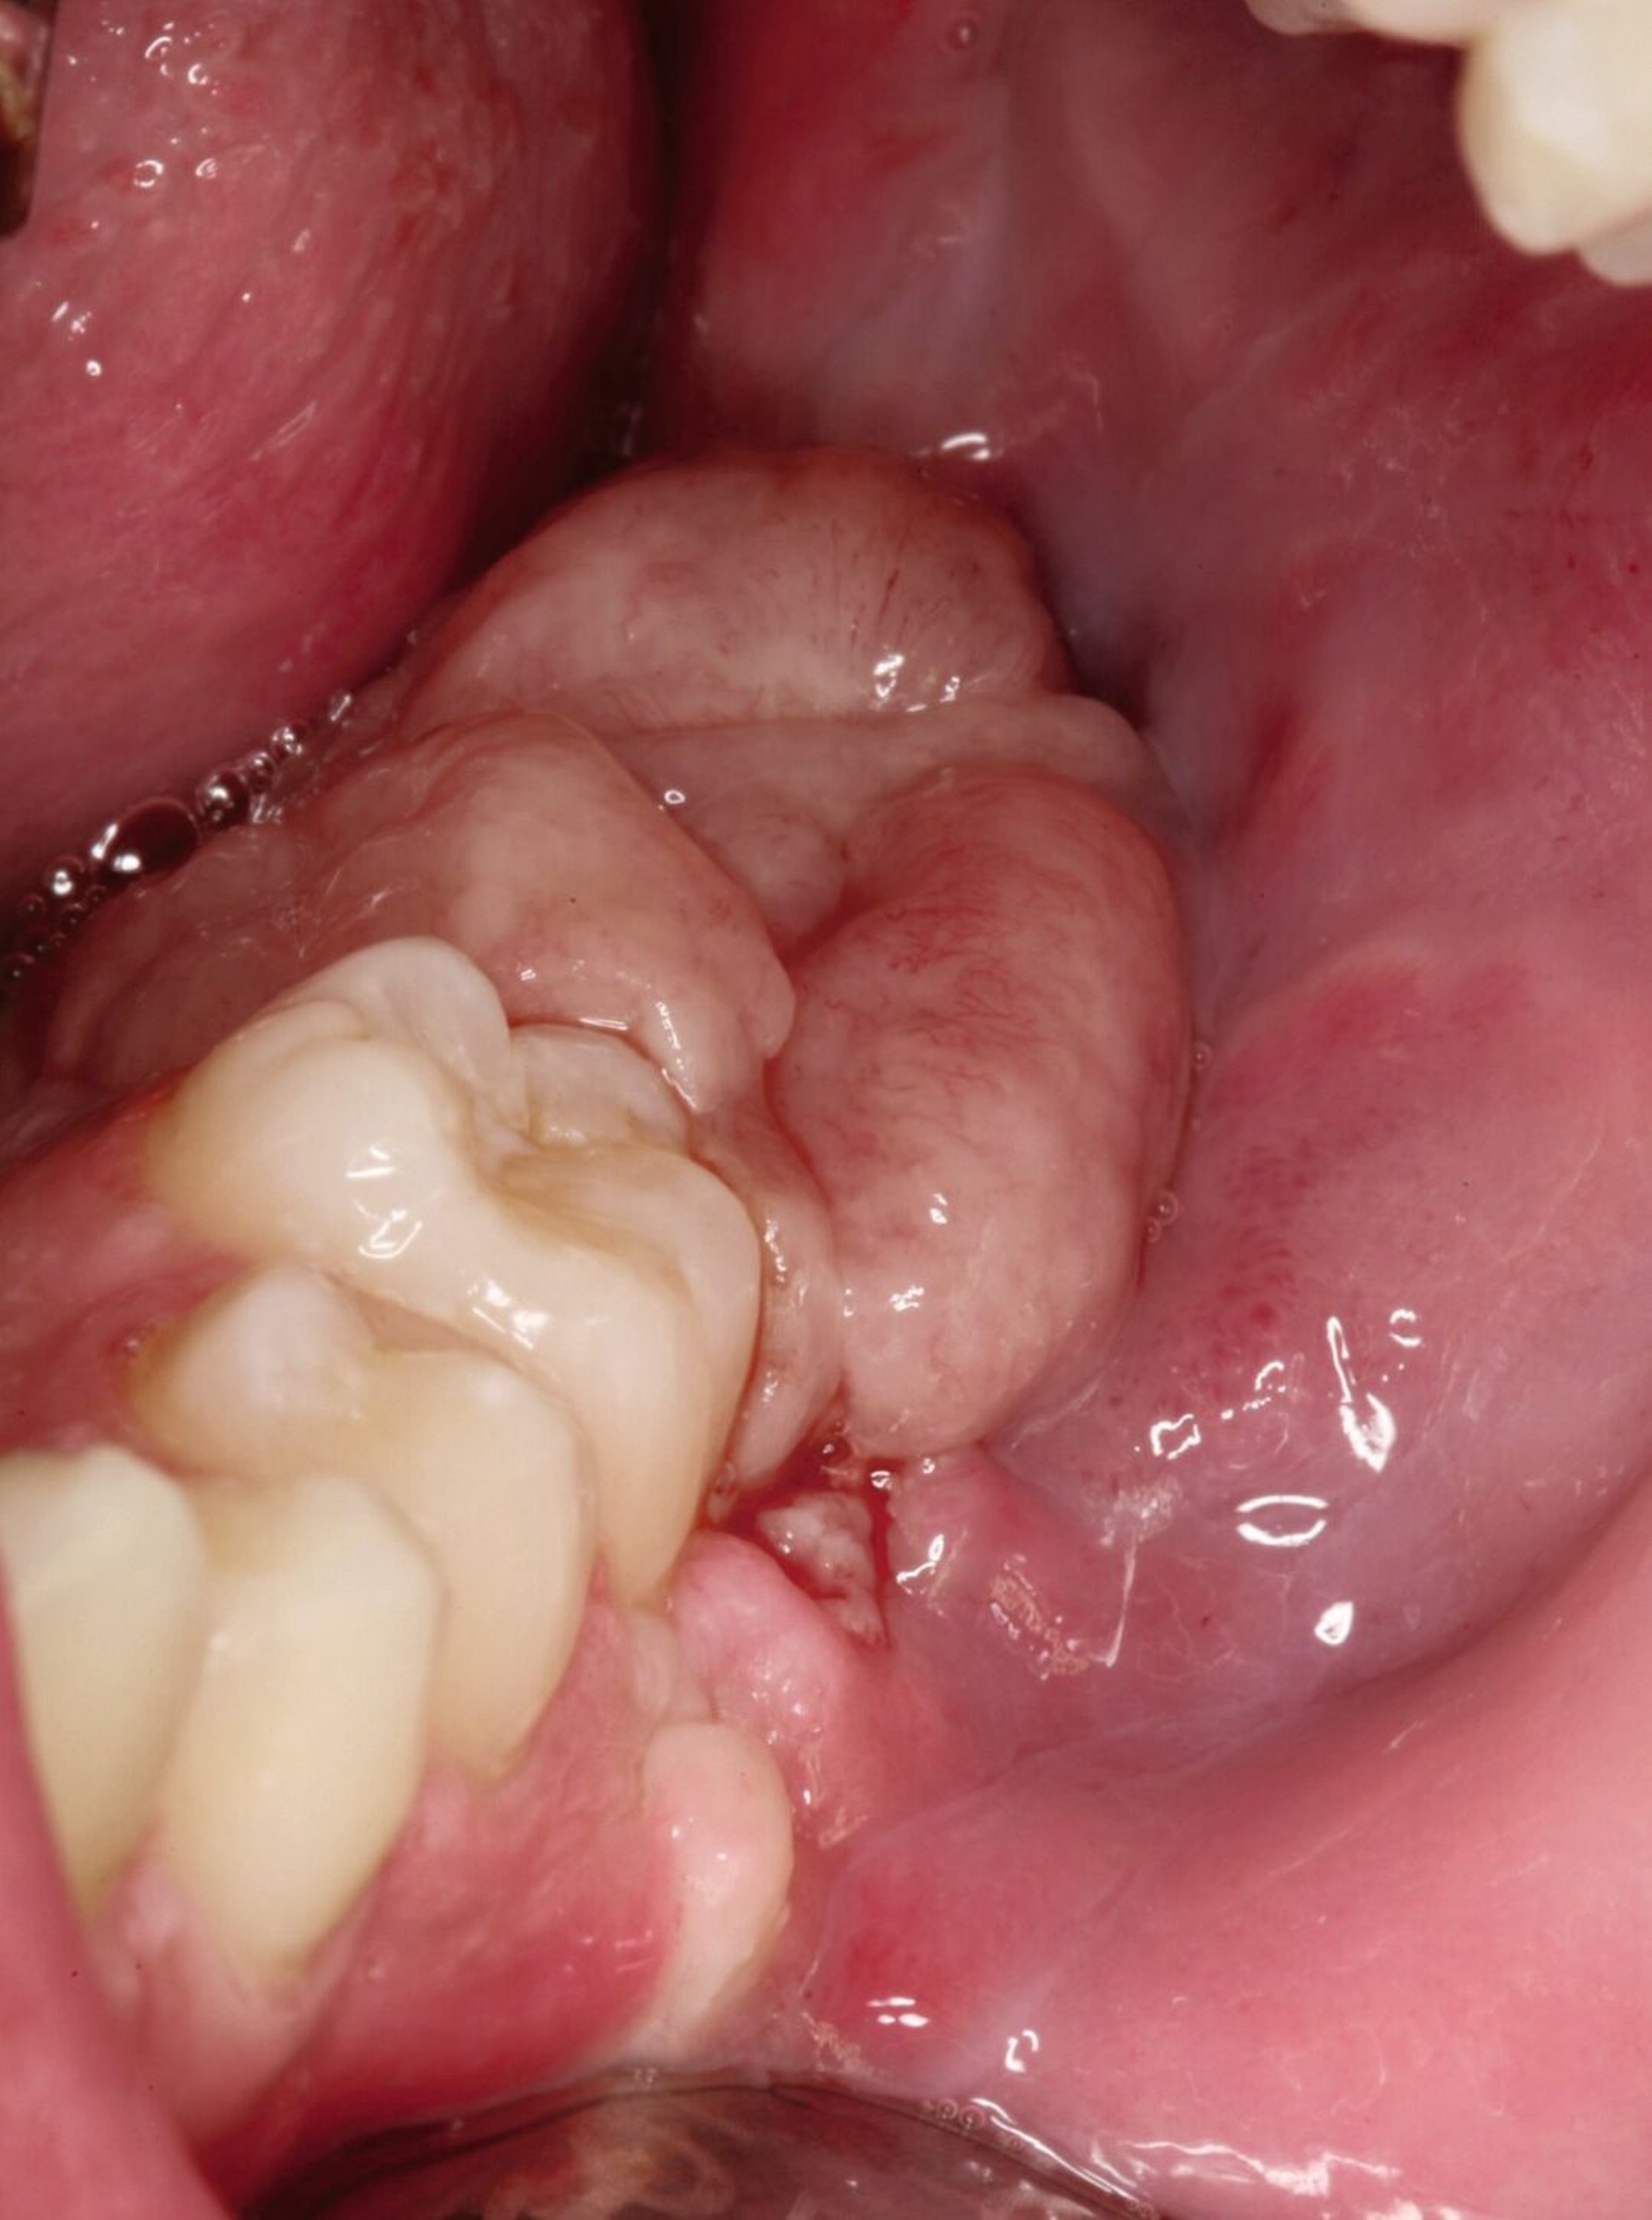

Ein 16-jähriger Junge stellte sich nach Überweisung durch seine behandelnde Kieferorthopädin aufgrund einer progredienten Schwellung des linken Unterkiefers in der Klinik und Poliklinik für Mund-, Kiefer- und Gesichtschirurgie vor. In der klinischen Untersuchung zeigte sich ein prominenter Befund distal der Zahnreihe mit hyperplastisch wirkender Schleimhaut (Abbildung 1).

Bei Verdacht auf das Vorliegen einer Keratozyste und zum Ausschluss eines Malignoms wurde die chirurgische Entfernung der Befunde in Intubationsnarkose durchgeführt. Hierbei erfolgte die Zystektomie beider Raumforderungen gemeinsam mit der Osteotomie der Zähne 37, 38, 47 und 48. Insbesondere in regio 38 zeigte der Befund eine direkte Kontinuität zwischen Knochen und Weichgewebe. Das Resektat wies eine gelbliche Farbe und eher weiche Konsistenz auf (Abbildung 4).